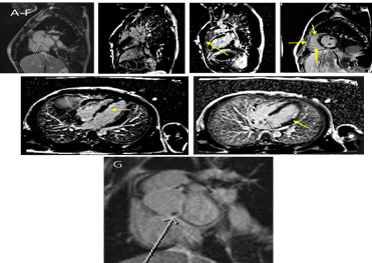

Mitral Valve Obstruction and Pulmonary Hypertension Caused by a Giant Left Atrial Myxoma Prolapsing in the Left Ventricle

Atrial myxomas are the most common primary cardiac tumors to diagnose. They are benign and have variable presentation. They have an excellent prognosis following surgical excision. We report a case of a 60 year old female who presented with initial signs of both right and left heart failure, fever and cough. Auscultation of the heart revealed an apical mid diastolic murmur. Trans-thoracic and trans-esophageal echocardiography revealed a pedunculated, giant left atrial myxoma that prolapsed through the mitral valve into the left ventricle in diastole producing functional mitral valve stenosis. The patient underwent a successful surgical excision of the tumor. The diagnosis and management of atrial myxomas is here reviewed.